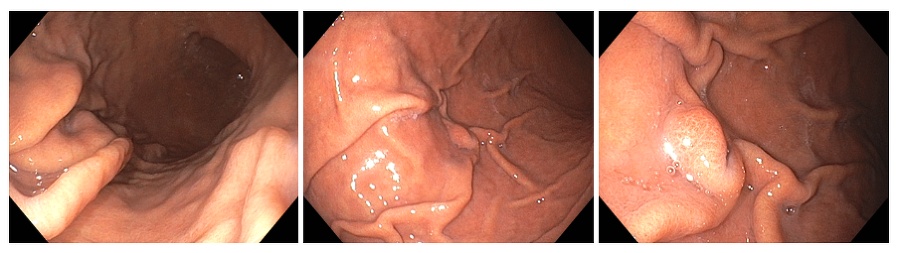

위궤양은 위내막이 손상되거나 염증이 생겨 위산과 소화액이 손상된 부위에 직접 접촉해 발생하는 속상한 질병입니다.

위궤양은 일반적으로 세 가지 치료 방법이 사용됩니다. 약물 치료, 영양 치료, 그리고 필요한 경우 수술까지 진행될 수 있습니다.